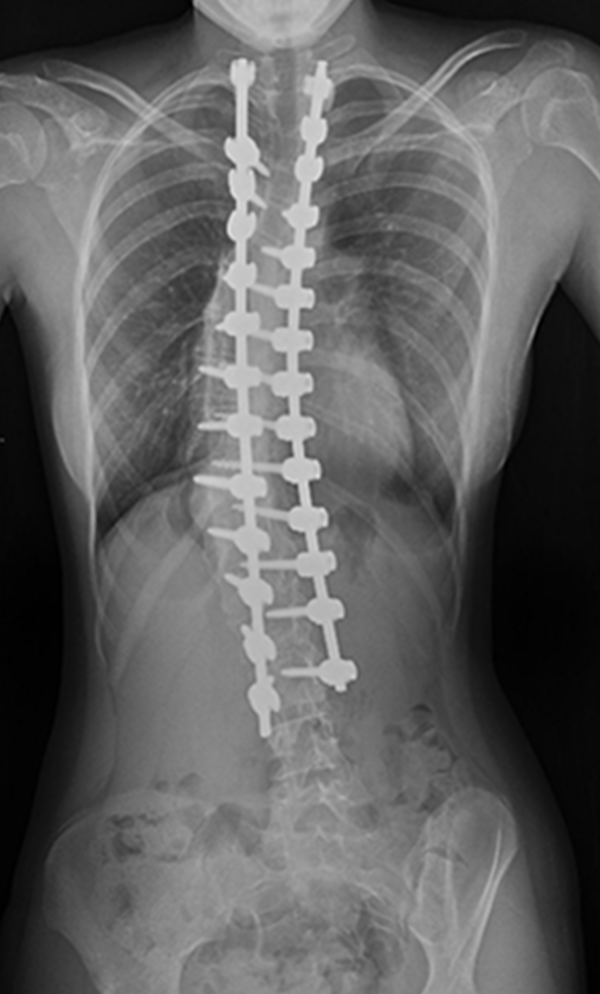

The procedure involves repositioning the spine and securing it with Screws and Rods. Bone graft is then placed so the treated vertebrae gradually heal together into one solid segment. This creates long-term stability, preventing further curve progression and improving overall alignment.

Gallery : Before - After

After

Before